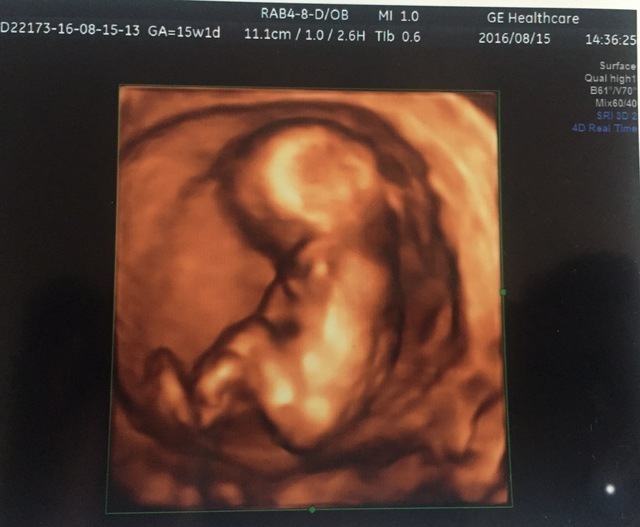

15週1日(15w1d・女の子)|yellowp さん(23歳)

エコー写真撮影時のエピソード:

全体がきれいにうつってるのはこの1枚です。1ヶ月後には写真ではおさまらない大きさに。恥ずかしがり屋でなかなか顔を見せてくれませんでした。

通っていた産科が3D?4D?だったので毎回見るのが楽しみでした。顔がはっきり見えるエコーがありますが、なんとなく面影があるかなという感じです。